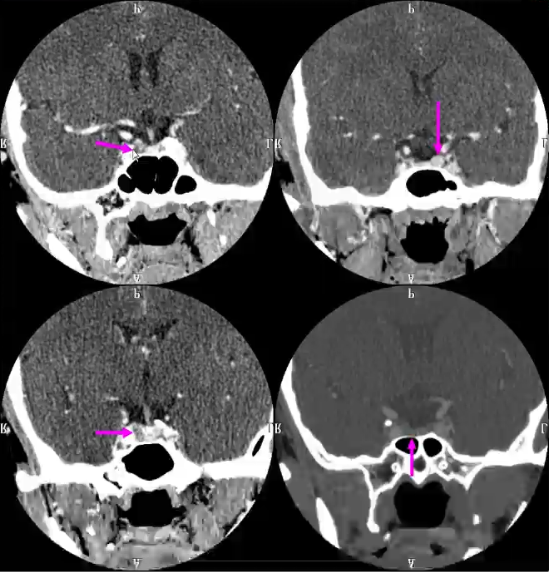

垂体瘤的CT表现:

1)蝶鞍扩大

2)直接征象:鞍内肿块,肿块呈等或略高密度,内常有低密度灶,均匀、不均匀或环形强化。平扫不易显示,增强呈等、低或稍高密度结节

3)间接征象:√垂体高度≥8mm √垂体上缘隆突 √垂体柄偏移 √鞍底下陷